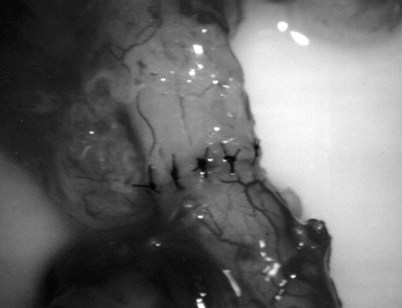

After opening the tunica vaginalis, the epididymis is inspected under the operating microscope. An anastomotic site is selected above the area of suspected obstruction, proximal to any visible sperm granulomas, where dilated epididymal tubules are clearly seen beneath the epididymal tunica (Fig. 22–29). A relatively avascular area is grasped with sharp jeweler’s forceps and the epididymal tunica tented upward. A 3- to 4-mm buttonhole is made in the tunica with microscissors to create a round opening that matches the outer diameter of the previously prepared vas deferens. The epididymal tubules are then gently dissected with a combination of sharp and blunt dissection until dilated loops of tubule are clearly exposed (Fig. 22–30). If the level of obstruction is not clearly delineated after the buttonhole opening is made in the tunic, a 70-µm diameter tapered needle from the 10-0 nylon microsuture is used to puncture the epididymal tubule beginning as distal as possible and fluid is sampled from the puncture site. When sperm are found, the puncture sites are sealed with microbipolar forceps, a new buttonhole is made in the epididymal tunic just proximally, and the tubule is prepared as described previously.

Figure 22–29 An anastomotic site is selected above the area of suspected obstruction, proximal to any visible sperm granulomas, where dilated epididymal tubules are clearly seen beneath the epididymal tunica, as marked by an arrow.

Figure 22–30 The epididymal tubules are then gently dissected with a combination of sharp and blunt dissection until dilated loops of tubule are clearly exposed.